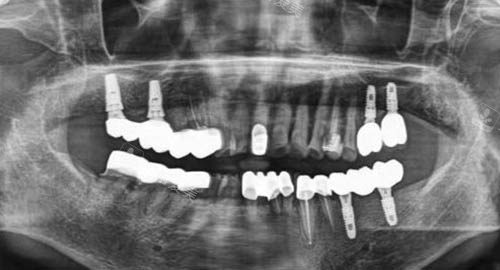

多颗牙齿种植ct

三、骨结合成功概率高的原因是什么?

该口腔医院骨结合成功概率高得益于靠前的技术和可靠医生的优质医术。

医院引进了头部的口腔种植技术,能够比较准地植入种植体,为骨结合创造良好的条件。

同时,医生团队都具备丰富的临床经验,他们会根据患者不同的口腔状况,制定个性化的种植方案,更准一些把握种植体的植入角度和深度。

在这样的支持下,大大提高了骨结合的成功概率,让患者能够更加安心地接受种植牙手术。